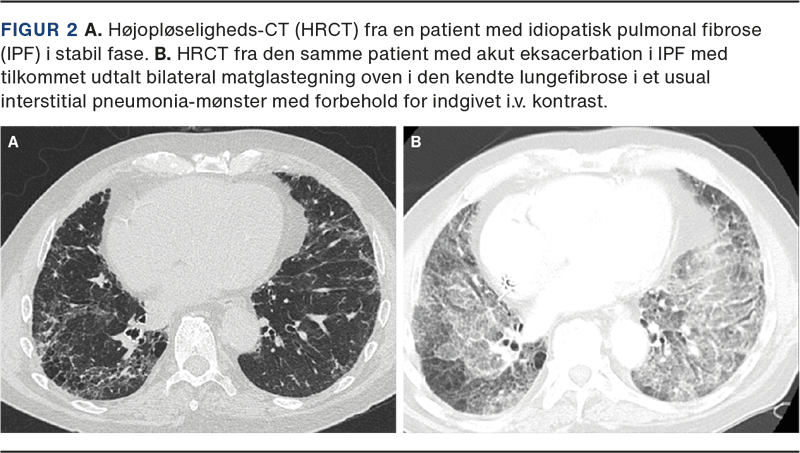

HRCT er nødvendig for at kunne stille diagnosen AE-IPF. Ved AE-IPF ses nyopstået bilateral matglastegning (hyppigst) og/eller konsolidering (sjældnere) oven i et underliggende kendt eller nydiagnosticeret usual interstitial pneumonia (UIP)-mønster (Figur 2) [10]. Disse radiologiske fund indgår i de diagnostiske kriterier for AE-IPF (Tabel 2) [2].

HRCT bør foretages før evt. CT af thorax med i.v. kontrast (alternativt SPECT/CT), som bruges til udelukkelse af lungeemboli [11]. CT af thorax med i.v. kontrast er ikke optimal til vurdering af matglastegning, idet kontrastindgift og den ofte manglende maksimale inspiration vanskeliggør vurdering af lungeparenkymet.